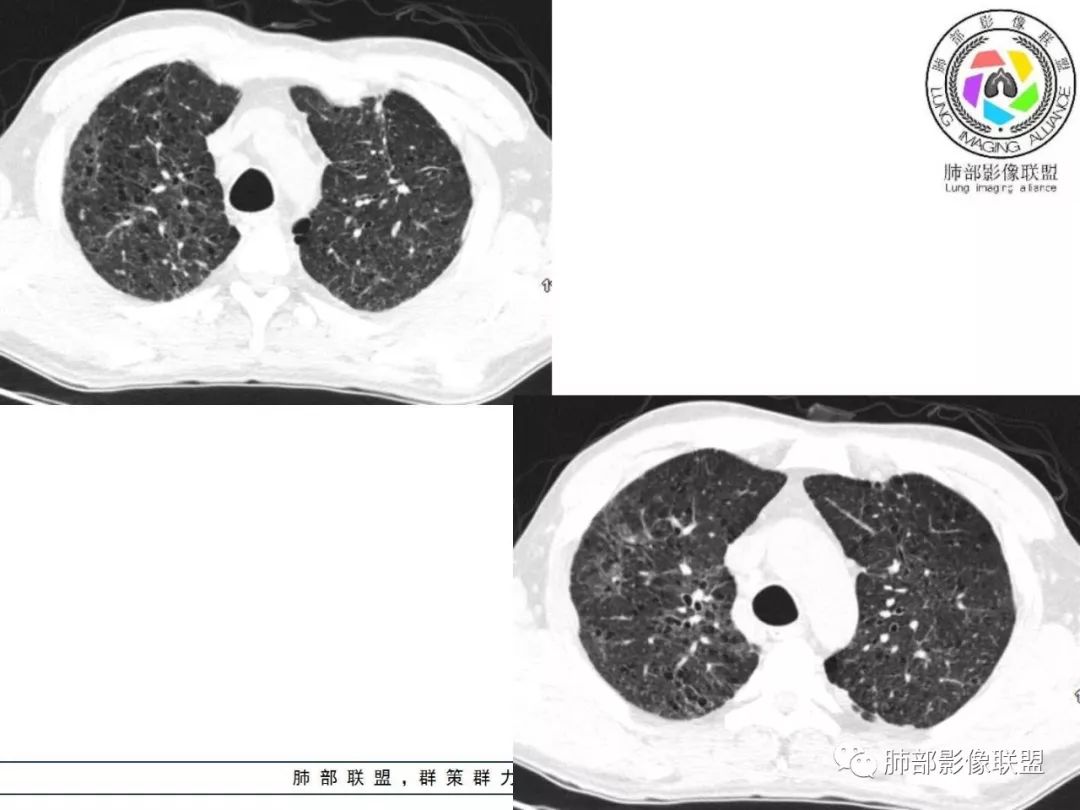

双肺间质性病变,中央间质增厚,胸膜下间质增厚,左侧胸膜肥厚,胸廓变小,肋间隙变窄。

对,大的支气管血管周围

胸部CT:两肺弥漫病灶,磨玻璃影,少许实变,部分累及胸膜,磨玻璃区可见囊?少许胸腔积液,两肺可见结节,支气管血管束增粗,小叶间隔增厚,支气管走形有扭曲扩张,可见纤维化。气肿、大泡。考虑:感染性病变,PCP?查下HIV,CD4,G等。鉴别结核、结缔组织病肺浸润。

病灶呈片状磨玻璃密度影,呈典型的烟花征。磨玻璃影密度偏高,有网结节样改变,与正常肺实质分界清楚,且常见相对高密度的勾画。

烟花征分为3肿类型:晕征、反晕征及均匀分布。

病变一般沿血管支气管束分布或小叶分布,一般上肺多于下肺(这与常见继发性肺结核分布相若)。

2. 肺气肿背景(小叶中心性肺气肿);双肺多发病灶整体沿血管支气管束及胸膜下分布,以上叶及下叶背段分布为主,有实变及GGO,边界清楚,有树芽,小叶间隔及中央间质增厚,叶间裂见到多发结节,部分支气管不规则牵拉扩张,提示病灶纤维化明显,结合临床病史,考虑病灶为间质性感染,肺门及纵隔内有钙化淋巴结,小叶间隔结节,考虑淋巴道增值性疾病可能,综合常规要怀疑间质性肺结核。